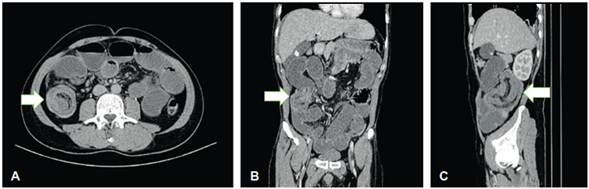

Presentamos el caso de un paciente de 47 años de edad, sin antecedentes quirúrgicos abdominales, con cuadro clínico de 72 horas de evolución de obstrucción intestinal parcial. Al examen físico no se detectaron masas palpables ni defectos de pared, y eran dudosos los signos de irritación peritoneal. La tomografía computarizada de abdomen y pelvis informó una imagen sugestiva de intususcepción ileocecal y signos de obstrucción intestinal mecánica (Figura 1).